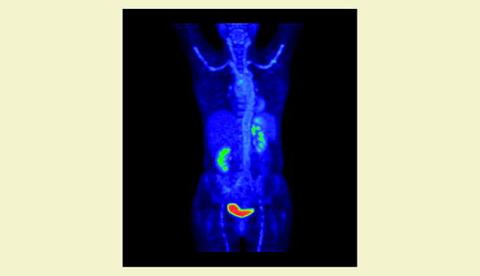

En 59-årig kvinde blev henvist fra et lokalt sygehus med langvarig, fluktuerende feber af ukendt årsag. Hun havde udtalt træthed og nedsat funktionsniveau i forhold til tidligere, men i øvrigt ingen fokale klager. En objektiv undersøgelse viste normale forhold, og der var ingen ømhed af aa. temporalis. Laboratorieundersøgelser havde vist sedimentationsreaktion 109 mm/time, C-reaktivt protein 143 mg/l og hæmoglobin 5,1 mmol/l. En computertomografi (CT) af thorax og abdomen viste ingen patologiske ændringer, og en ekkokardiografi var normal. Videre udredning med positronemissionstomografi (PET)/CT blev planlagt. Under indlæggelsen fik patienten tyggeclaudicatio, hvilket foranledigede henvisning til biopsi af a. temporalis.

Billedet viser resultatet af PET/CT med fluordeoxyglukose (FDG)-optagelse i samtlige centrale arterier, dvs. aorta, aa. iliacae, aa. femoralis, aa. subclaviae samt aa. carotis, hvilket er foreneligt med panarteritis. Efter start af prednisolon indtrådte der hurtig subjektiv bedring, og efterfølgende svar fra temporalisbiopsi bekræftede diagnosen kæmpecellearteritis. Ved en kontrol-PET/CT en måned senere sås der let regression.

Konklusion: FDG-PET er en ny og effektiv undersøgelse til at påvise udbredelsen og graden af kæmpecellearteritis, i særdeleshed ved stærkt forhøjede fasereaktanter [1, 2].